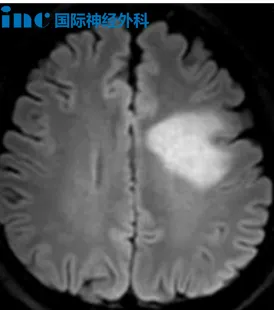

患者常出现头晕、头痛、复视等症状,当地医院检查怀疑脱髓鞘病变,经治疗后症状加重,赴北京进一步行PET核磁检查考虑低级别胶质瘤,建议穿刺活检明确诊断。患者及家属常存在疑问:"当前医学技术先进,为何脑瘤需通过活检手术确诊,而多数患者无需活检也可接受治疗"。此情况临床常见,简而言之,这属于"因患者个体差异、疾病特性、时机因素及治疗需求"而不同的决策问题。通俗而言,疾病明确诊断通常经历以下步骤:

其次为病变定位,通常通过非侵入性检查如实验室检验、影像学检查进行排查定位。部分疾病研究较为明确,通过影像学即可确诊,如脑出血、脑梗死、脑海绵状血管瘤、动脉瘤、脑膜瘤等疾病,影像诊断可达明确标准。尽管先进影像学技术对颅内病变诊断具有重要意义,但部分病变因影像表现不典型,无法通过影像特征做出临床诊断,必须经过活检或手术获得更具体病理学诊断,以指导后续靶向治疗和预后判断。

田先生体检偶然发现颅内占位性病变。当时无任何身体不适,各项检查正常,医生建议保守观察。半年后MRI显示左侧放射冠、半卵圆中心、胼胝体区多发占位性病变,肿瘤性病变可能性较大。医生告知:病灶位置深在,术后偏瘫失语风险极高。是否手术?田先生陷入犹豫,期间出现强直性癫痫大发作。为寻求手术机会,他咨询巴教授。得到可手术答复后,田先生仍选择先行活检再决定治疗方向。取得活检结果后再访巴教授,教授回复提示:活检并非必须!一次手术既可切除肿瘤又能明确病理,何必分两次进行?巴教授远程评估指出:立体定向活检有时获取组织样本量少,可能仅取到病灶边缘而非肿瘤中心。因取材不足可能导致结果不准确,故不百分之百依赖该诊断结果。尤其当活检样本量少时,给出最终诊断并非易事。手术可在不造成新功能缺损前提下切除病变,为保留言语和运动功能,不过度激进切除,尽量保留功能。